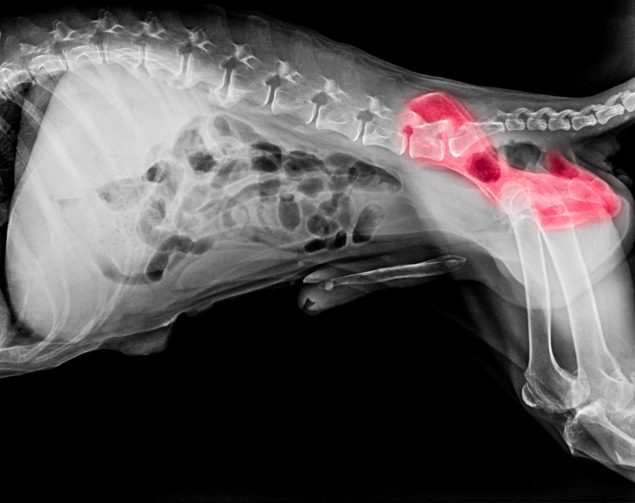

Hüftdysplasie Hund

Was tun bei Hüftproblemen?Hüftdysplasie beim Hund ist eine genetische Erkrankung, die alle Hunderasse treffen kann. Bei dieser Hüftkrankheit kommt es zu Verformungen am Hüftgelenk. Die Folge davon ist unter anderem, dass der Hund nur noch unter Schmerzen gehen kann.

Während Gelenkpfanne und Gelenkkopf bei gesunden Hunden passgenaue Gegenstücke sind, sind die Gelenke bei der Hüftdysplasie eures Hundes verformt. Der Hund kann sich in der Folge nicht richtig bewegen, da es im Laufe der Zeit zu schmerzhaftem Abrieb an Knochen und Knorpel (sogenannte Arthrose) oder zu Knochenwucherungen kommt.